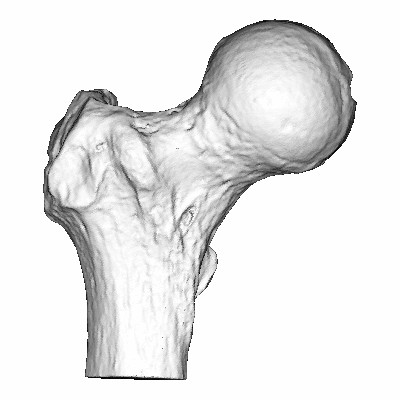

Please annotate this diagram with the site(s) of swelling or tenderness.

Right Knee

Notes: -

Left Knee

Notes:-